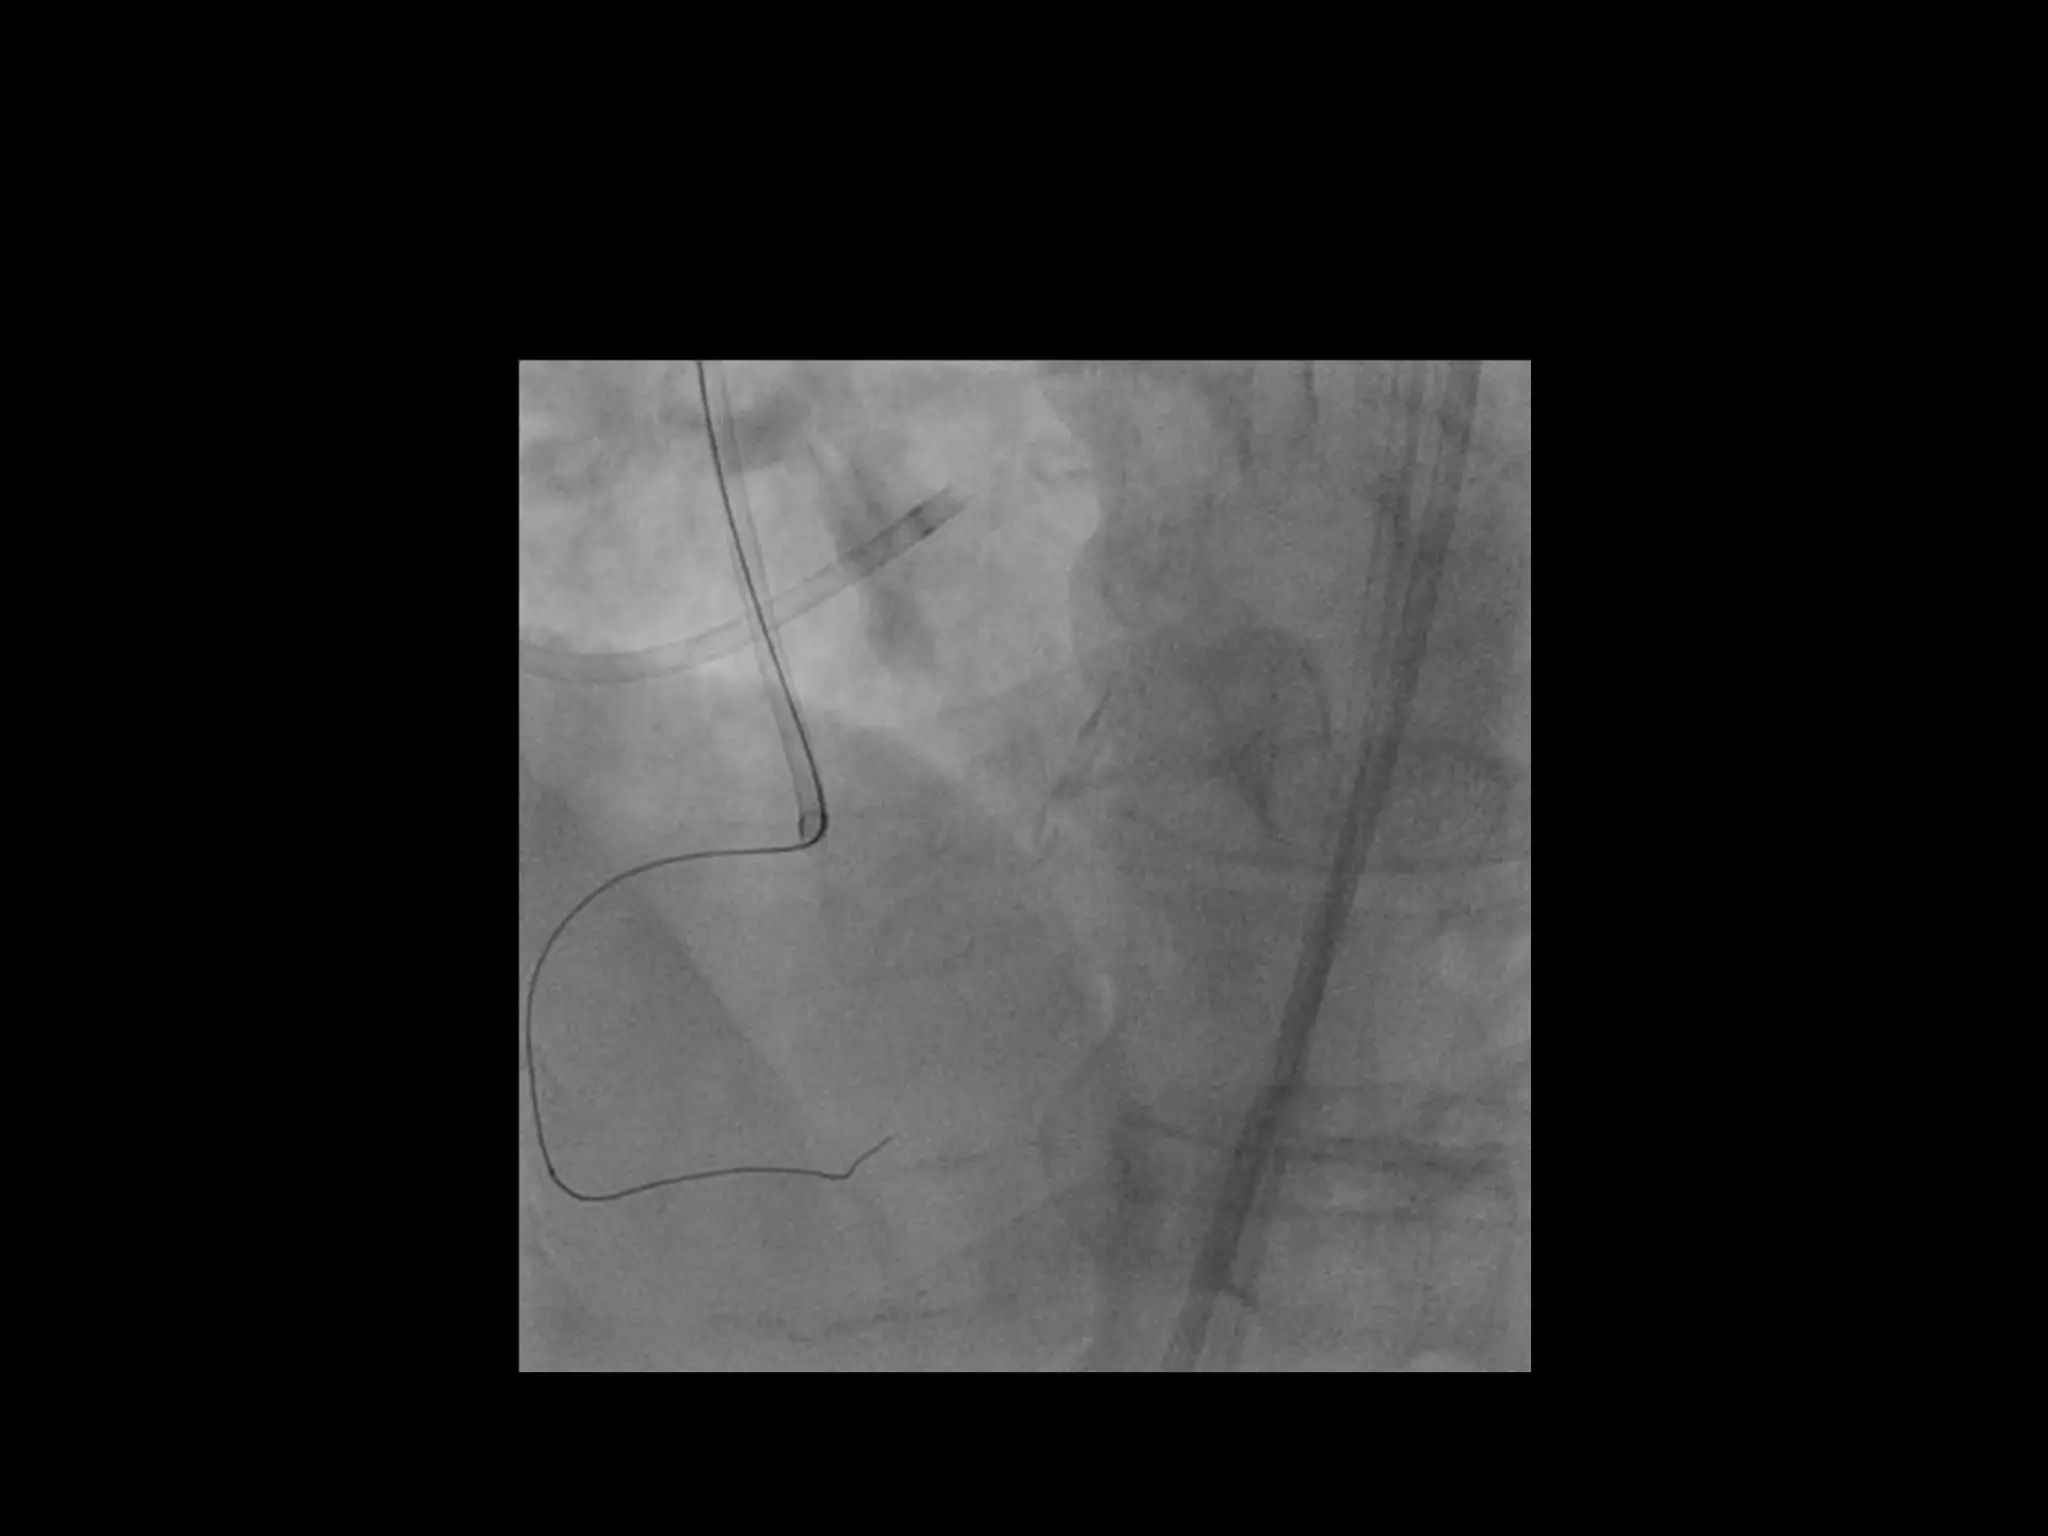

This document provides guidance on evaluating the feasibility of percutaneous coronary intervention (PCI) for a chronic total occlusion (CTO). Key factors to consider include: the patient's tolerance for a long procedure, contrast load, and radiation exposure; the CTO's proximal cap ambiguity, length, distal landing zone, and presence of interventional collaterals; and ensuring good quality angiography. With adequate planning and use of appropriate CTO techniques, feasibility is nearly always present for symptomatic patients. Success rates of CTO-PCI are reported to be 94% when using a planned approach.